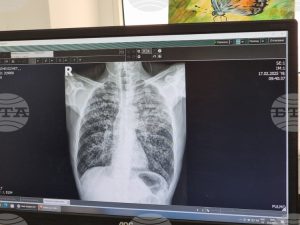

УМБАЛ „Д-р Георги Странски“ в Плевен стартира безплатна кампания за оценка на риска от белодробна туберкулоза през декември_69316854e5183.jpeg